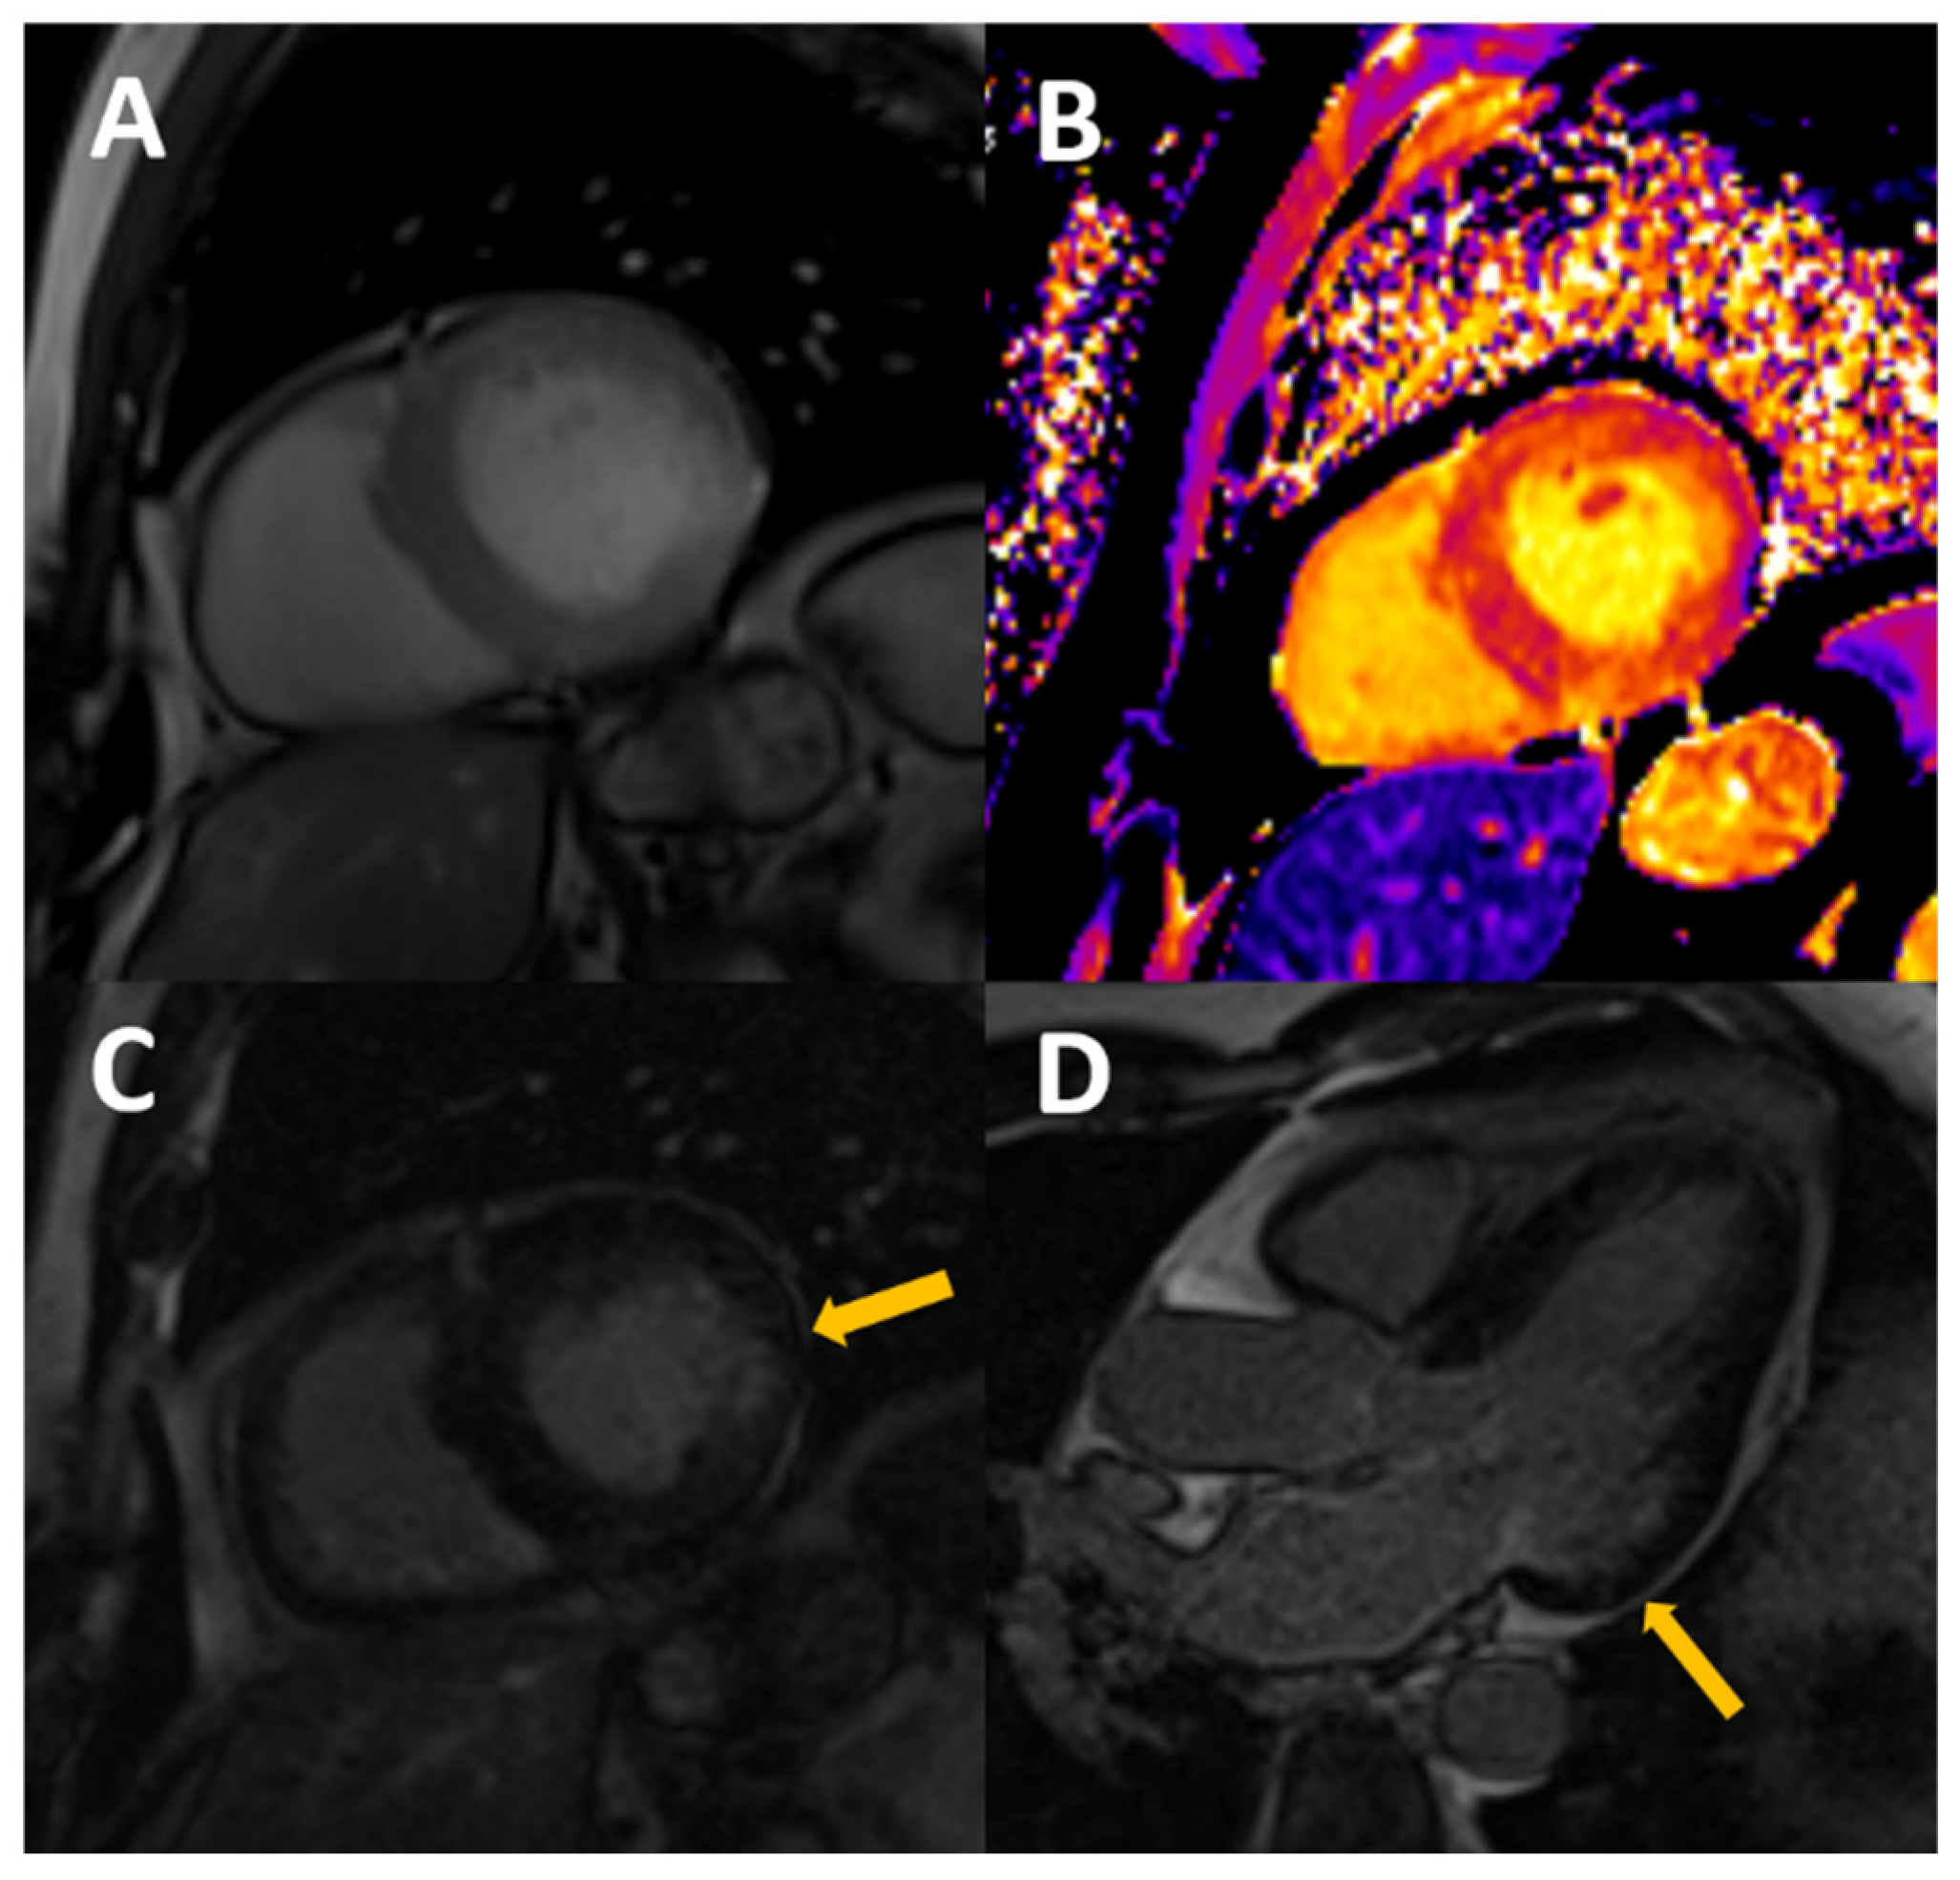

Figure 2.

54-year-old male, with stage III CKD secondary to nefroangiosclerosis, who presents with CMR concentric LVH in cine images (A), mildly increased native T1 (B) with normal T2, probably reflecting appropriate volume status with some degree of diffuse fibrosis. A previously unknown myocardial infarction is present as a subendocardial scar in mid-basal segments of the inferolateral wall (arrows in C,D).

Figure 3.

Typical findings of uremic cardiomyopathy with CMR. The patient presents with mild pericardial effusion, severe concentric LVH with hypertrophy of papillary muscles (A), diffuse intramyocardial LGE (B), and diffuse fibrosis, as shown by high values of native T1 (C) and ECV (post contrast T1, D).